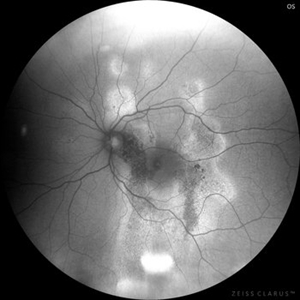

Chronic Central Serous Chrorioretinopathy

Oct 28 2022 by Selene Rodríguez-Castro, MD

Fundus autofluorescence of a 43-year-old man with chronic central serous chrorioretinopathy, with recurrent episodes since 2020.

Photographer: Selene Rodríguez-Castro, APEC

Imaging device: clarus zeiss

Condition/keywords: chronic central serous chorioretinopathy (CSCR)